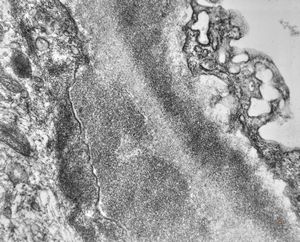

M,22y. | type II membranoproliferative glomerulonephritis